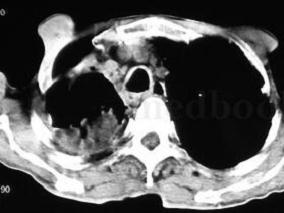

1小时条评论一、病史摘要 患者,男性,61岁,农民,因反复咳嗽、咳痰、咯血25天于2011年8月11日入院。患者25天前感冒后出现咳嗽,咳少量白色黏痰,伴呼吸困难、头晕,无头痛、发热、咯血,至当地诊所输液治疗。2天后,患者咳嗽更加频繁,痰量较前渐增多,并出现痰中带鲜红色血...